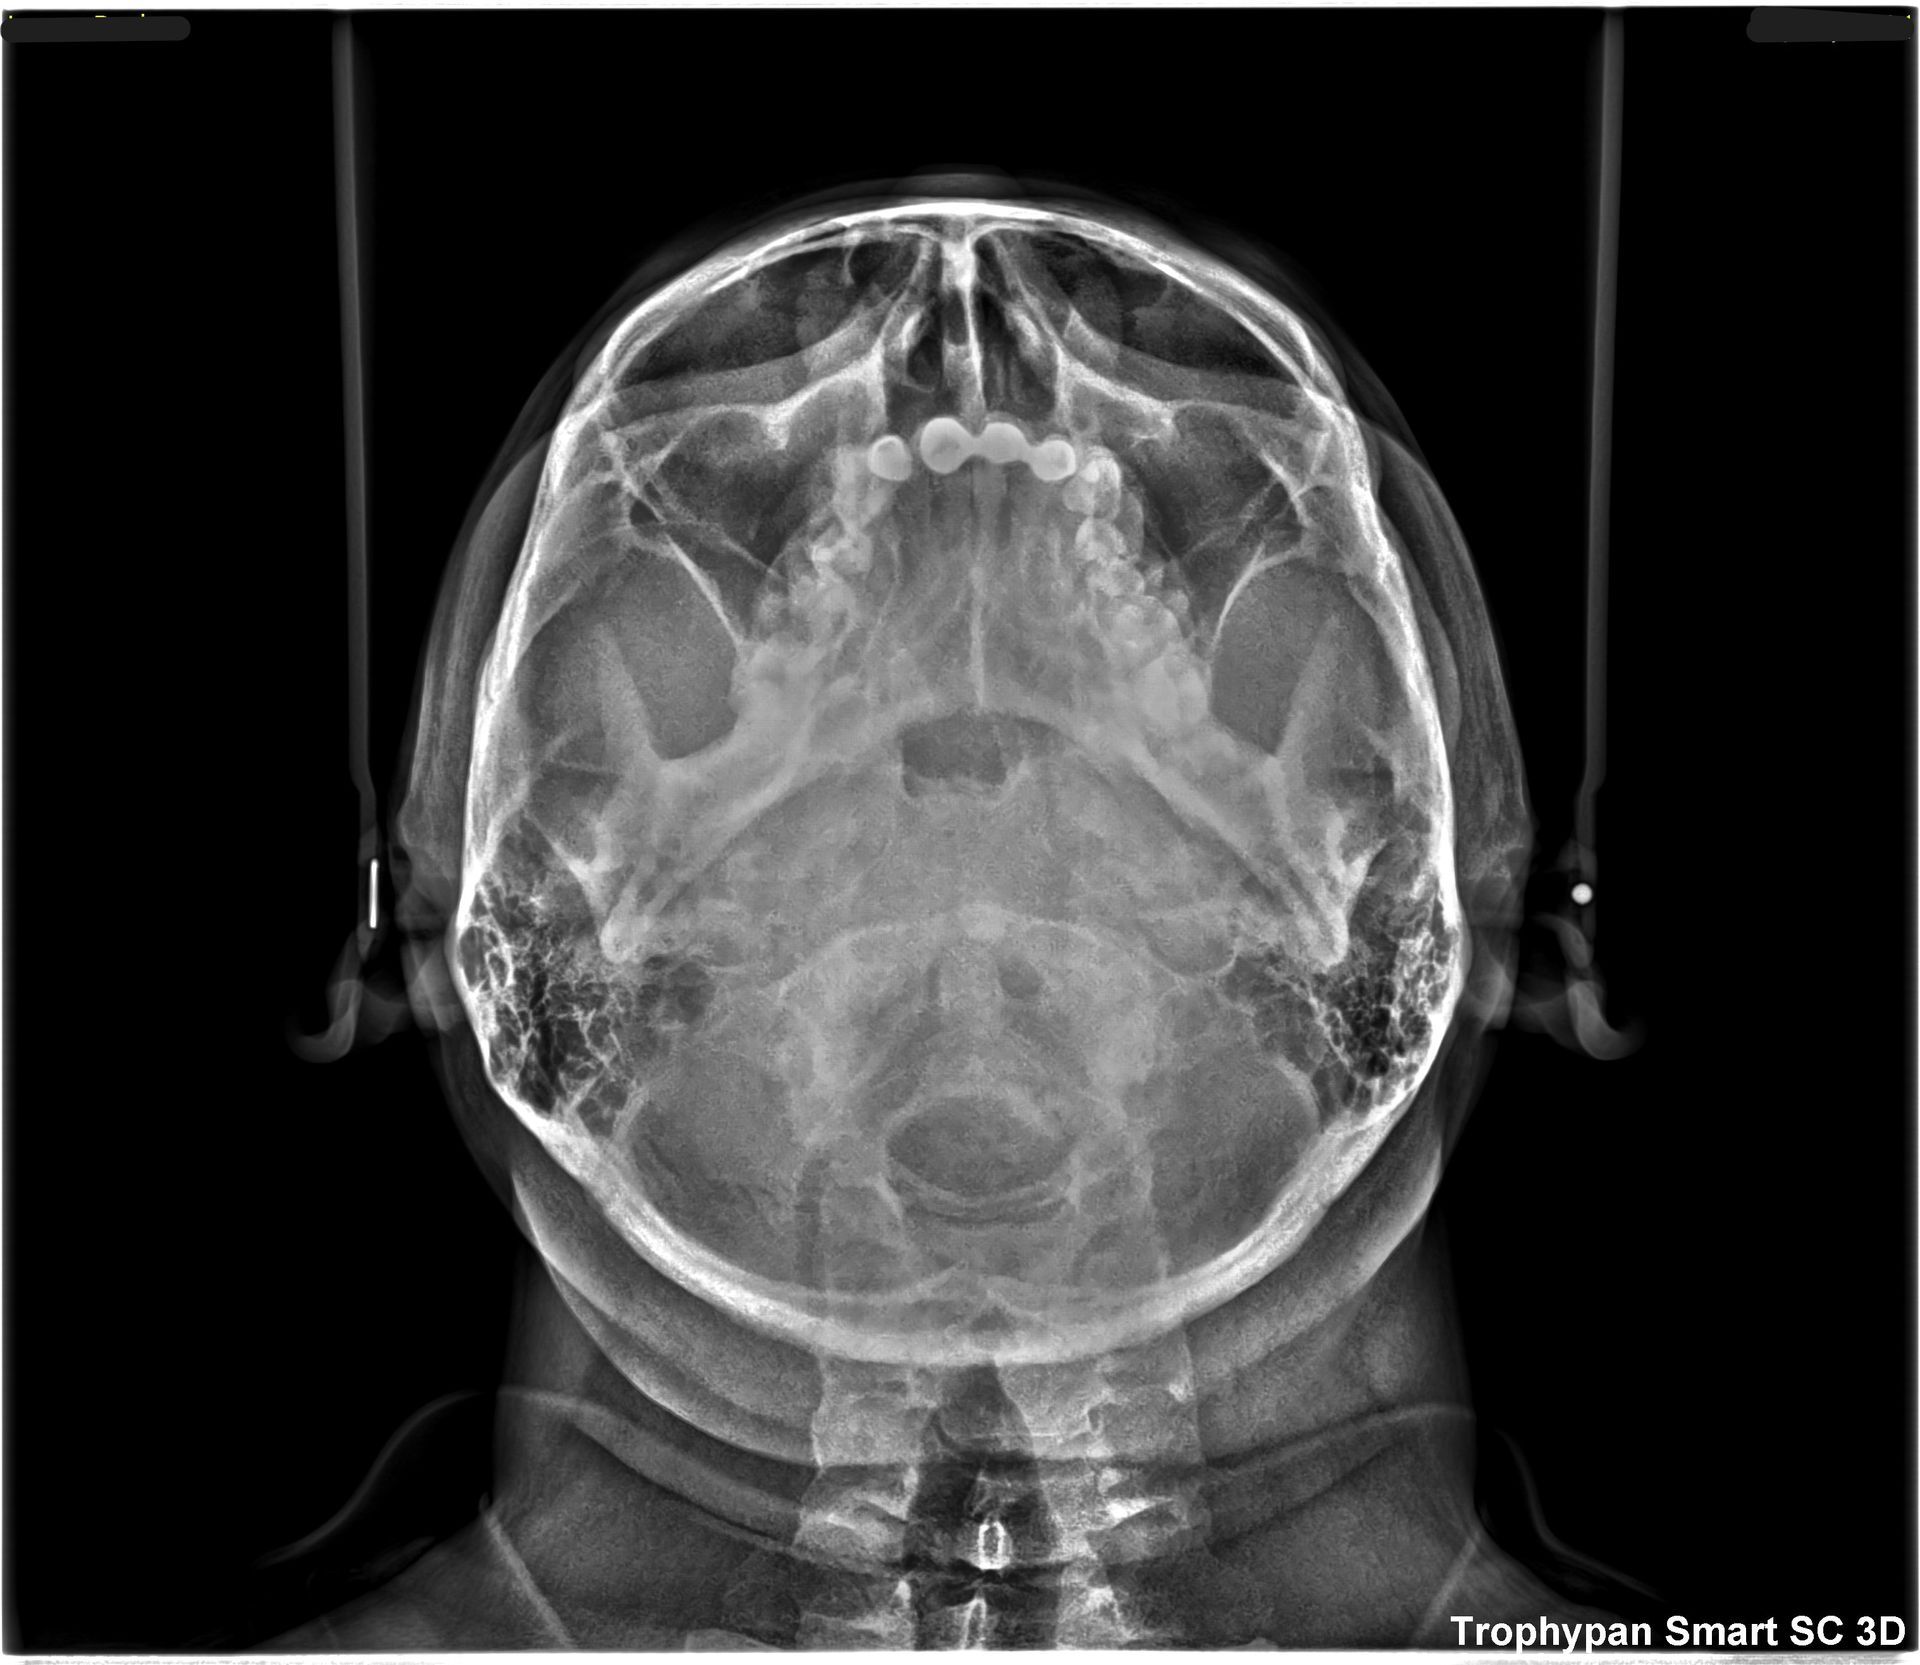

Uno de nuestros principales servicios es la adquisición de imágenes dentales 2D y 3D, fundamentales para un diagnóstico preciso y una planificación adecuada de tratamientos dentales.

Contamos con tecnología avanzada que nos permite obtener imágenes claras y detalladas de la boca y los tejidos circundantes, lo que es crucial para evaluar la salud dental y detectar posibles problemas.